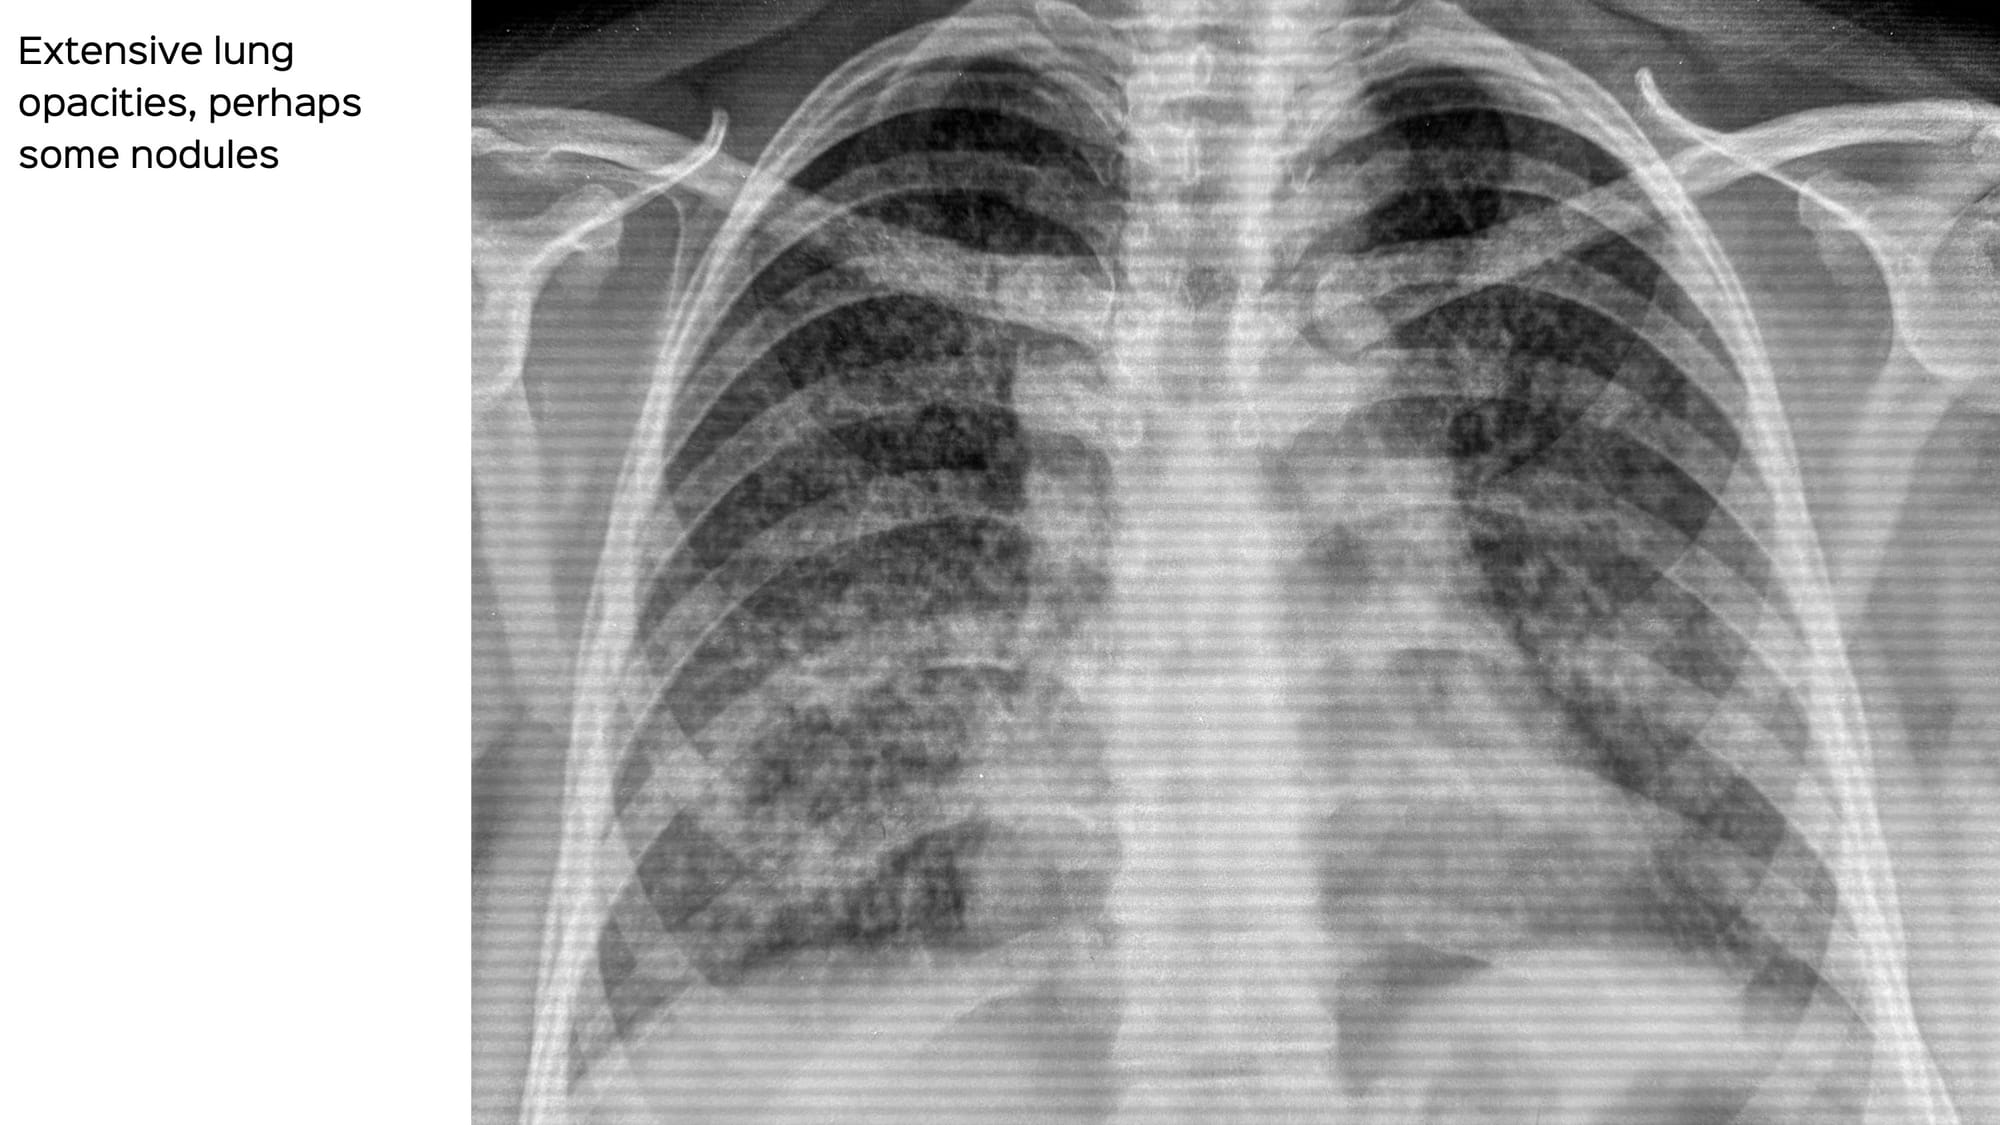

A 38-years old came with acute respiratory failure.

The chest radiograph showed diffuse disease.